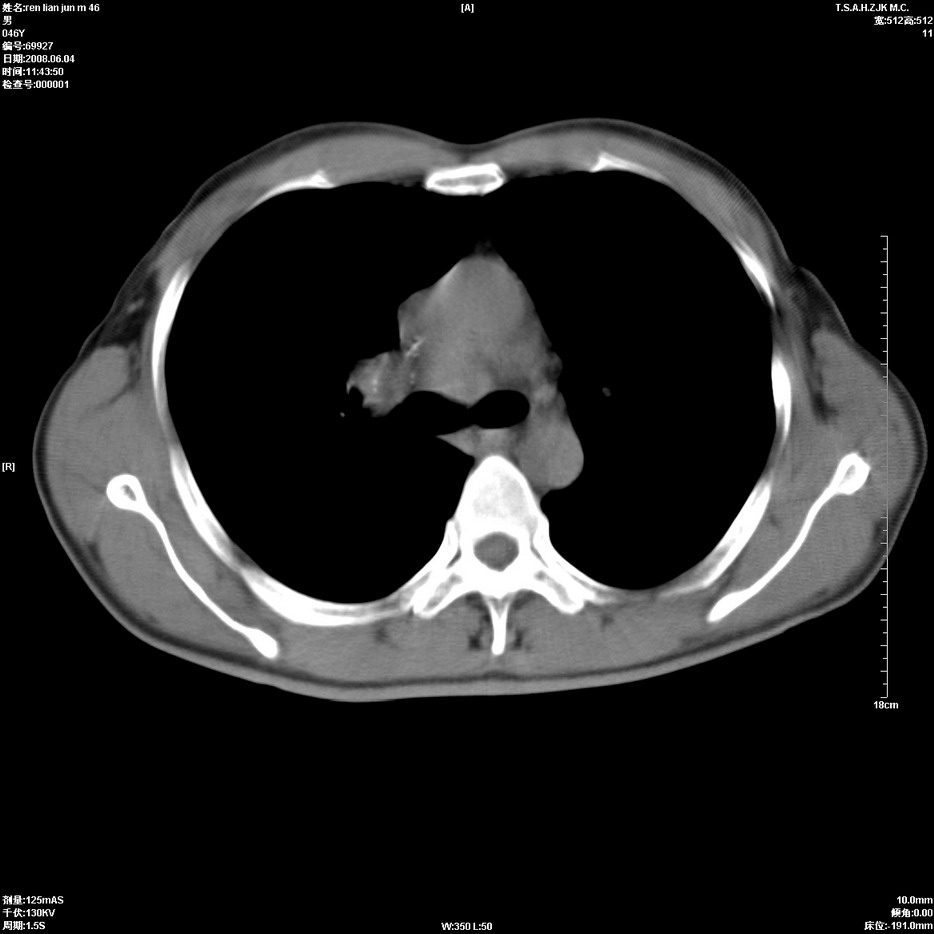

以下是引用qiu999在2008-6-5 17:14:00的发言:[br]考虑右肺中心型肺癌.颅内应做增强检查.

以下是引用形影不离在2008-6-5 19:18:00的发言:[br]右肺中心型肺癌并纵隔及左侧腋窝淋巴结转移,颅内应做增强检查。

以下是引用杀毒软件在2008-6-5 18:33:00的发言:[br]支持考虑右肺中心型肺癌,颅内病变是不是转移,不好说